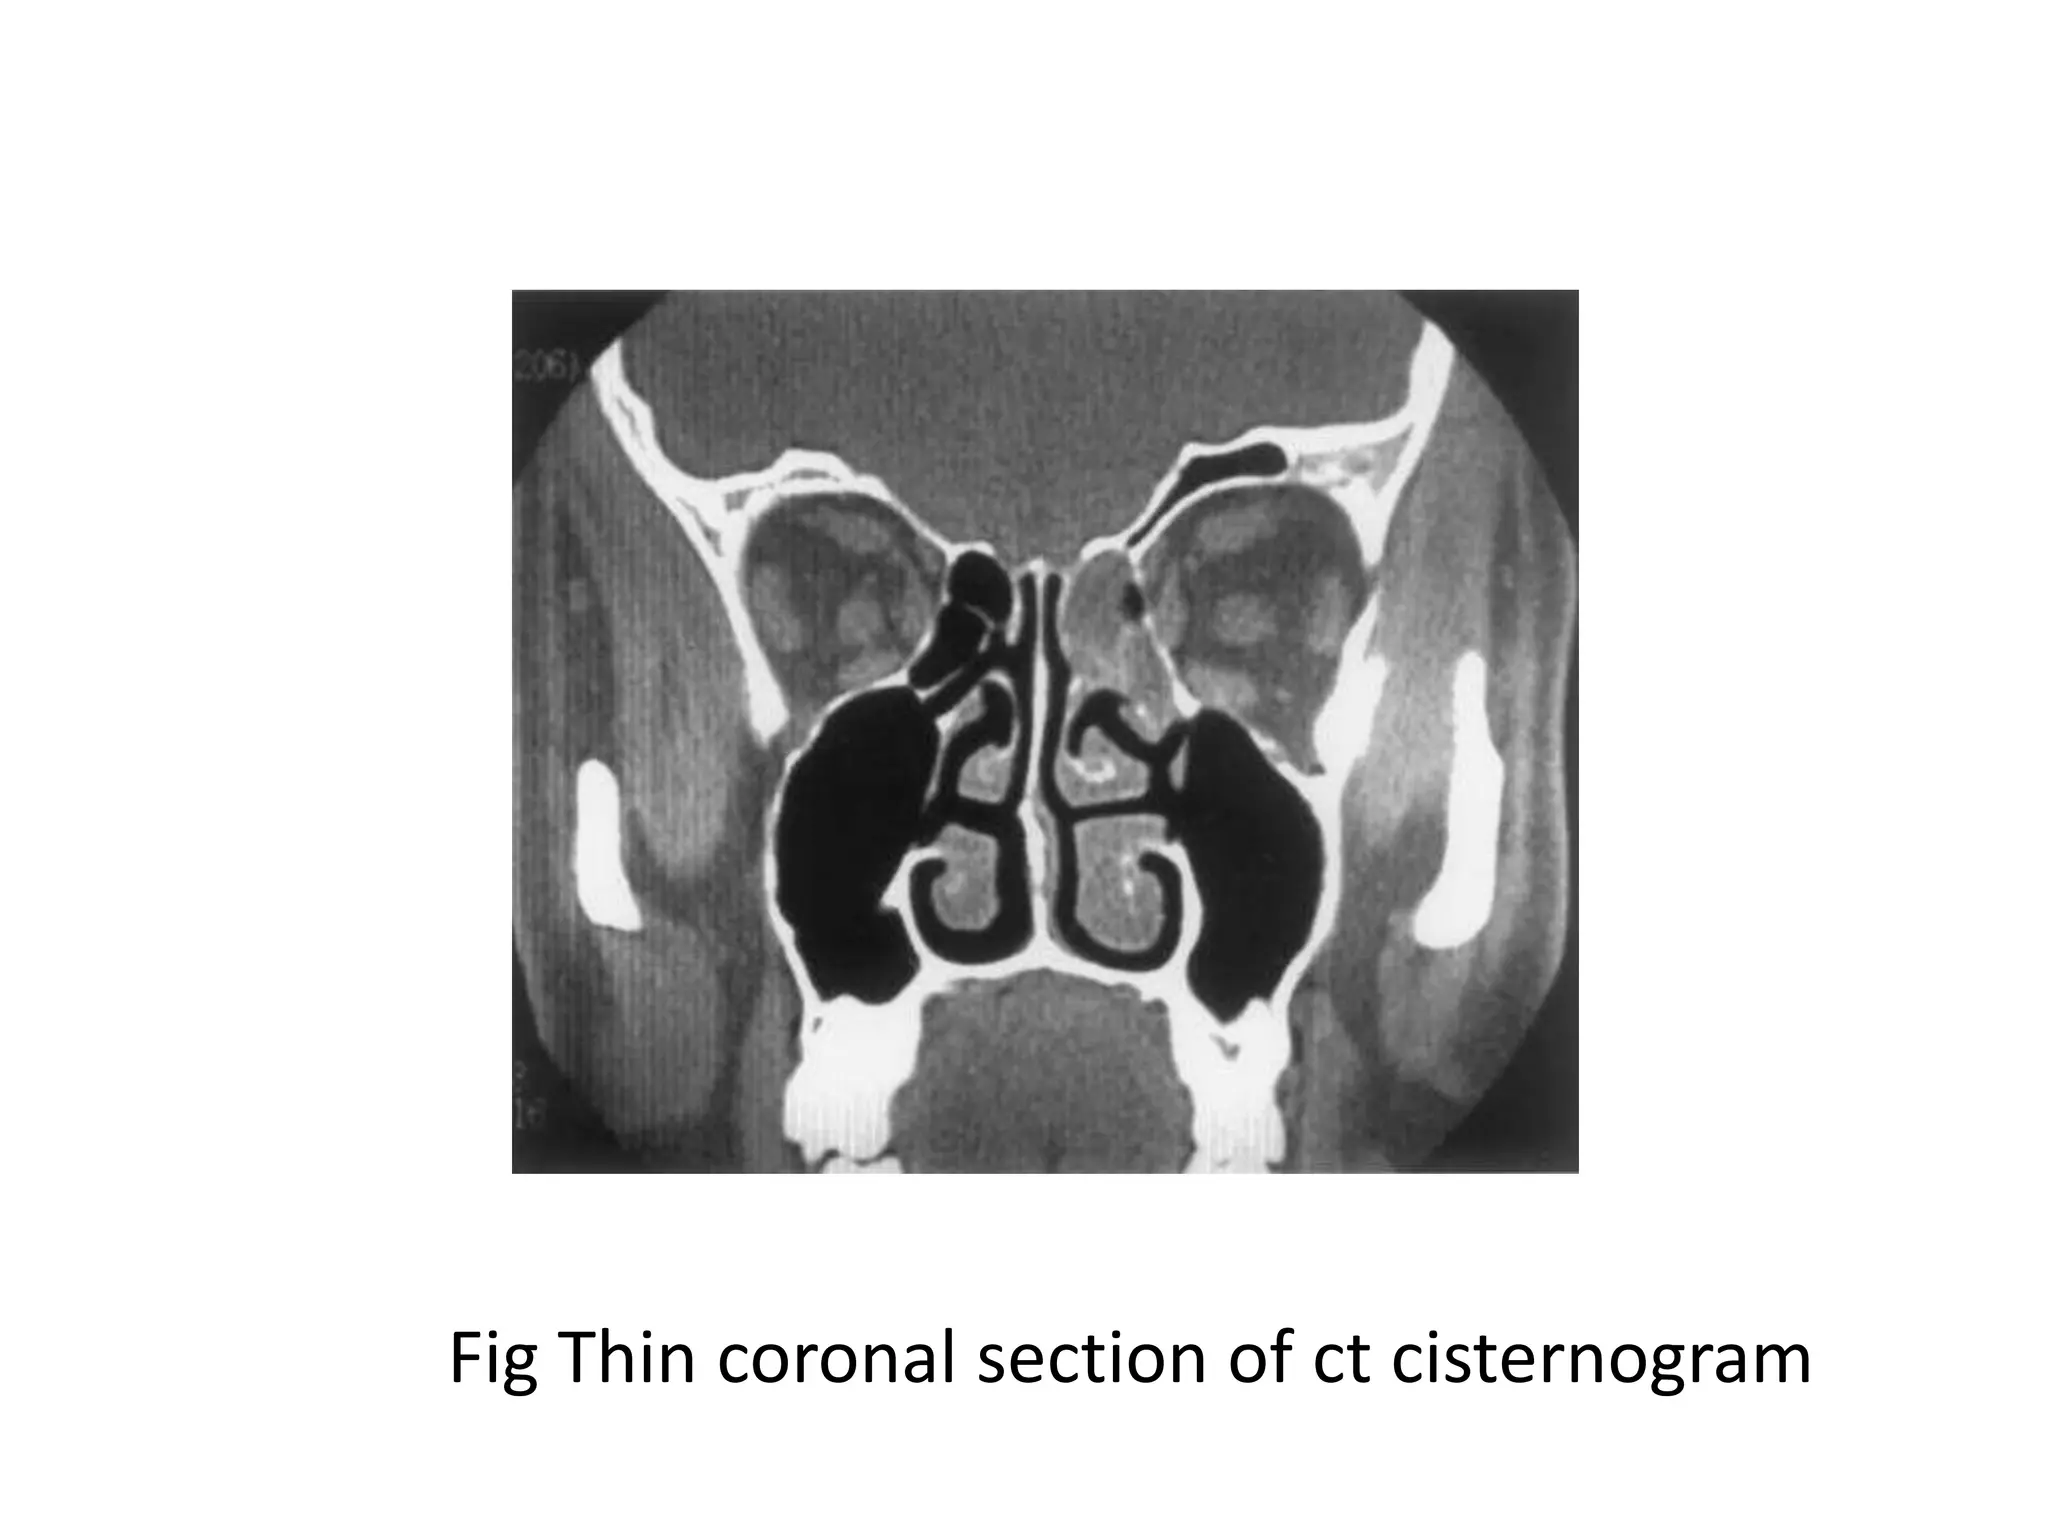

Fig: Thin coronal section of ct cisternogram

Fig Thin coronal section of ct cisternogram

Fig: Thin coronalsection of ct cisternogram

Fig Thin coronalsection of ct cisternogram